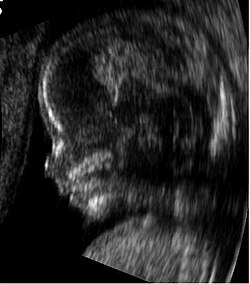

U praktičnoj medicini ultrazvuk se primjenjuje u liječenju različitih reumatskih bolesti (ultrasonoterapija), u dijagnostici, osobito u opstetriciji (razvoj zametka, mnogostruka trudnoća, promjene placente i drugo) i u kardiologiji. Svojstva nekoga tkiva mogu se utvrditi na temelju brzine kojom se ultrazvuk širi u tkivu. Otpor što ga širenju ultrazvuka pružaju tkiva može se pretvaranjem odbijenih ultrazvučnih valova u električne impulse pratiti na zaslonu uz pomoć elektroničkih uređaja (ehokardiografija; ehooftalmografija; ehosonografija ili ultrasonografija; encefalografija).